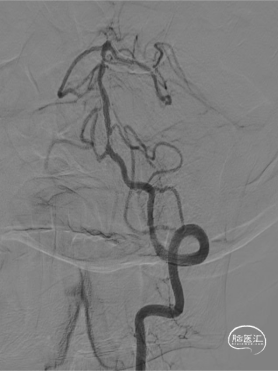

➢ 脑血管造影检查

患者老年女性,反复头晕,有高血压病史,DSA提示“基底动脉下段重度狭窄”,药物保守治疗,头晕反复发作,有支架置入指征。拟采用“球囊扩张后,自膨支架置入”治疗。

通桥白驹®颅内球囊扩张导管2.25*15mm到位扩张。

通桥白驹®颅内球囊扩张导管扩张完后。

0.027" 支架微导管到位,提示在真腔。

4.0*16mm自膨颅内支架到位并打开过程。

支架置入后造影。

左侧锁骨下造影情况。